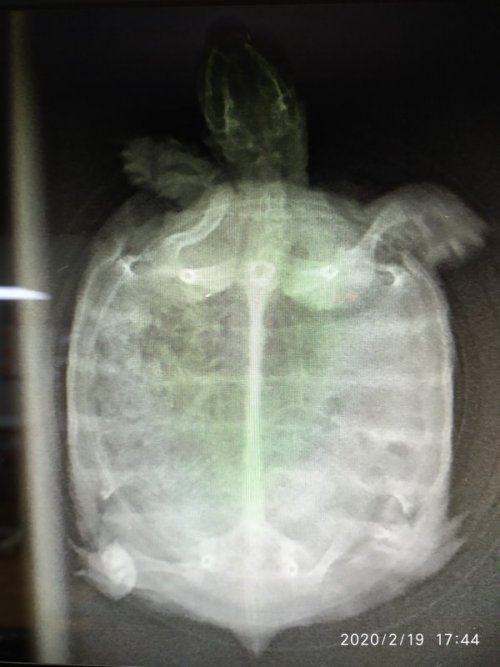

@AlekSandra рентген - дорсо-вентральная проекция + латеральная(боковая) (левая)

Сделали рентген.

Я сейчас выкладываю фото поменьше размером, иначе они не проходят ограничение форума, если какой-то нужен будет покрупнее, скажите я выложу отдельно.

@AlekSandra  в жкт, особенно в желудке, присходит что-то нечто. Переполнен и с большим кол-вом газов, это и давит на легкие (особенно левое)

по этим снимкам пневмонии нет.